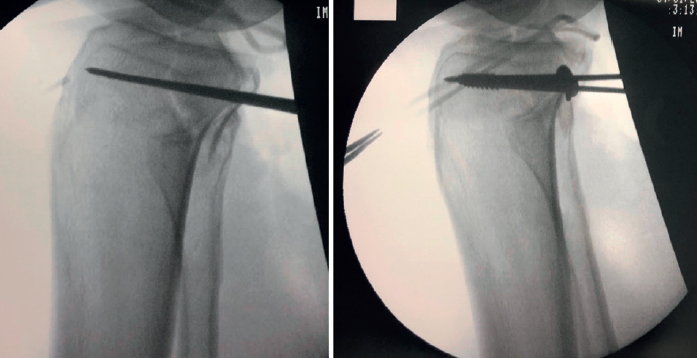

Frosch(14) propone un abordaje posterolateral, en decúbito prono lateralizado rotando parcialmente al lado externo de la cadera y la extremidad afectas (Figura 6). Una vez disecado el nervio ciático poplíteo externo (CPE), este abordaje permite el trabajo en 2 ventanas longitudinales que exponen la meseta tibial posteroexterna tanto en su porción más anterior como posterior al ligamento lateral externo. Además del CPE, otra estructura vasculonerviosa que hay que tener en cuenta es la arteria tibial anterior. Esta emerge de la arteria poplítea para hacerse anterior en su paso a través de la membrana interósea tibioperonea. Este cayado condiciona enormemente el espacio útil de trabajo (5-6 cm) y, por tanto, el tipo de material de osteosíntesis a utilizar (Figuras 7, 8 y 9).

Figura 7. Doble ventana posteroexterna. Disección ciático poplíteo externo. Síntesis con placa en ventana anterior, síntesis con tornillos canulados en ventana posterior controlando la reducción.

Figura 8. Fractura en margen posterolateral. Control radiológico tras la síntesis utilizando el abordaje de Frosch.